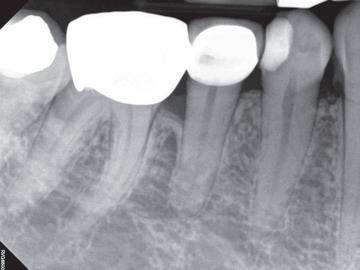

Høykonsentrert tyntflytende kalsiumhydroksidpasta med >41% hydroksid i en konsistens som enkelt appliseres med en liten og fleksibel plastkanyle: Flexi-Tip. Autoklavérbare Flexi-Tip i kombinasjon med den myke konsistensen sparer deg for tid, og hjelper deg å oppnå en presis og dyp applisering. pH 12,4 gjør den baktericid. Langvarig. Røntgenkontrast. 589,-

Høykonsentrert kalsiumhydroksid på >41%. pH 12,4 gir høy antibakteriell effekt, bakteriedrepende. Røntgenkontrast. Langvarig. Klar til bruk, appliseres direkte gjennom steril kanyle.

Calasept EDTA

Skyllevæske til kjemisk utvidelse av rotkanaler. Letter den mekaniske utrenskningen. Leveres med adapter til skyllesprøyten. Nå 250ml.

2% Klorhexidindiglukonat. Benyttes etter EDTA ved revisjonsbehandlinger og alle typer nekrosebehandlinger. Nå 250ml.